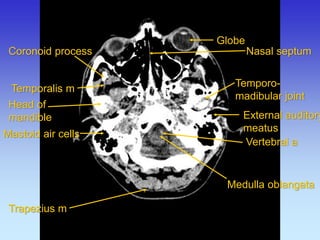

External auditory meatus

Mastoid air cells

Medulla oblangata

Nasal septum

Temporalis m

Trapezius m

Coronoid process

Head of mandible

Temporo- madibular joint

Globe

Vertebral a